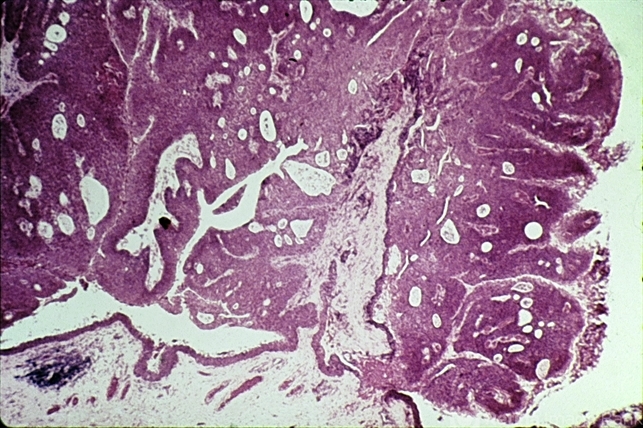

- papilloma, conjunctiva, acanthosis

- Papilloma of the conjunctiva showing fronds of acanthotic epithelium with central fibrovascular cores.